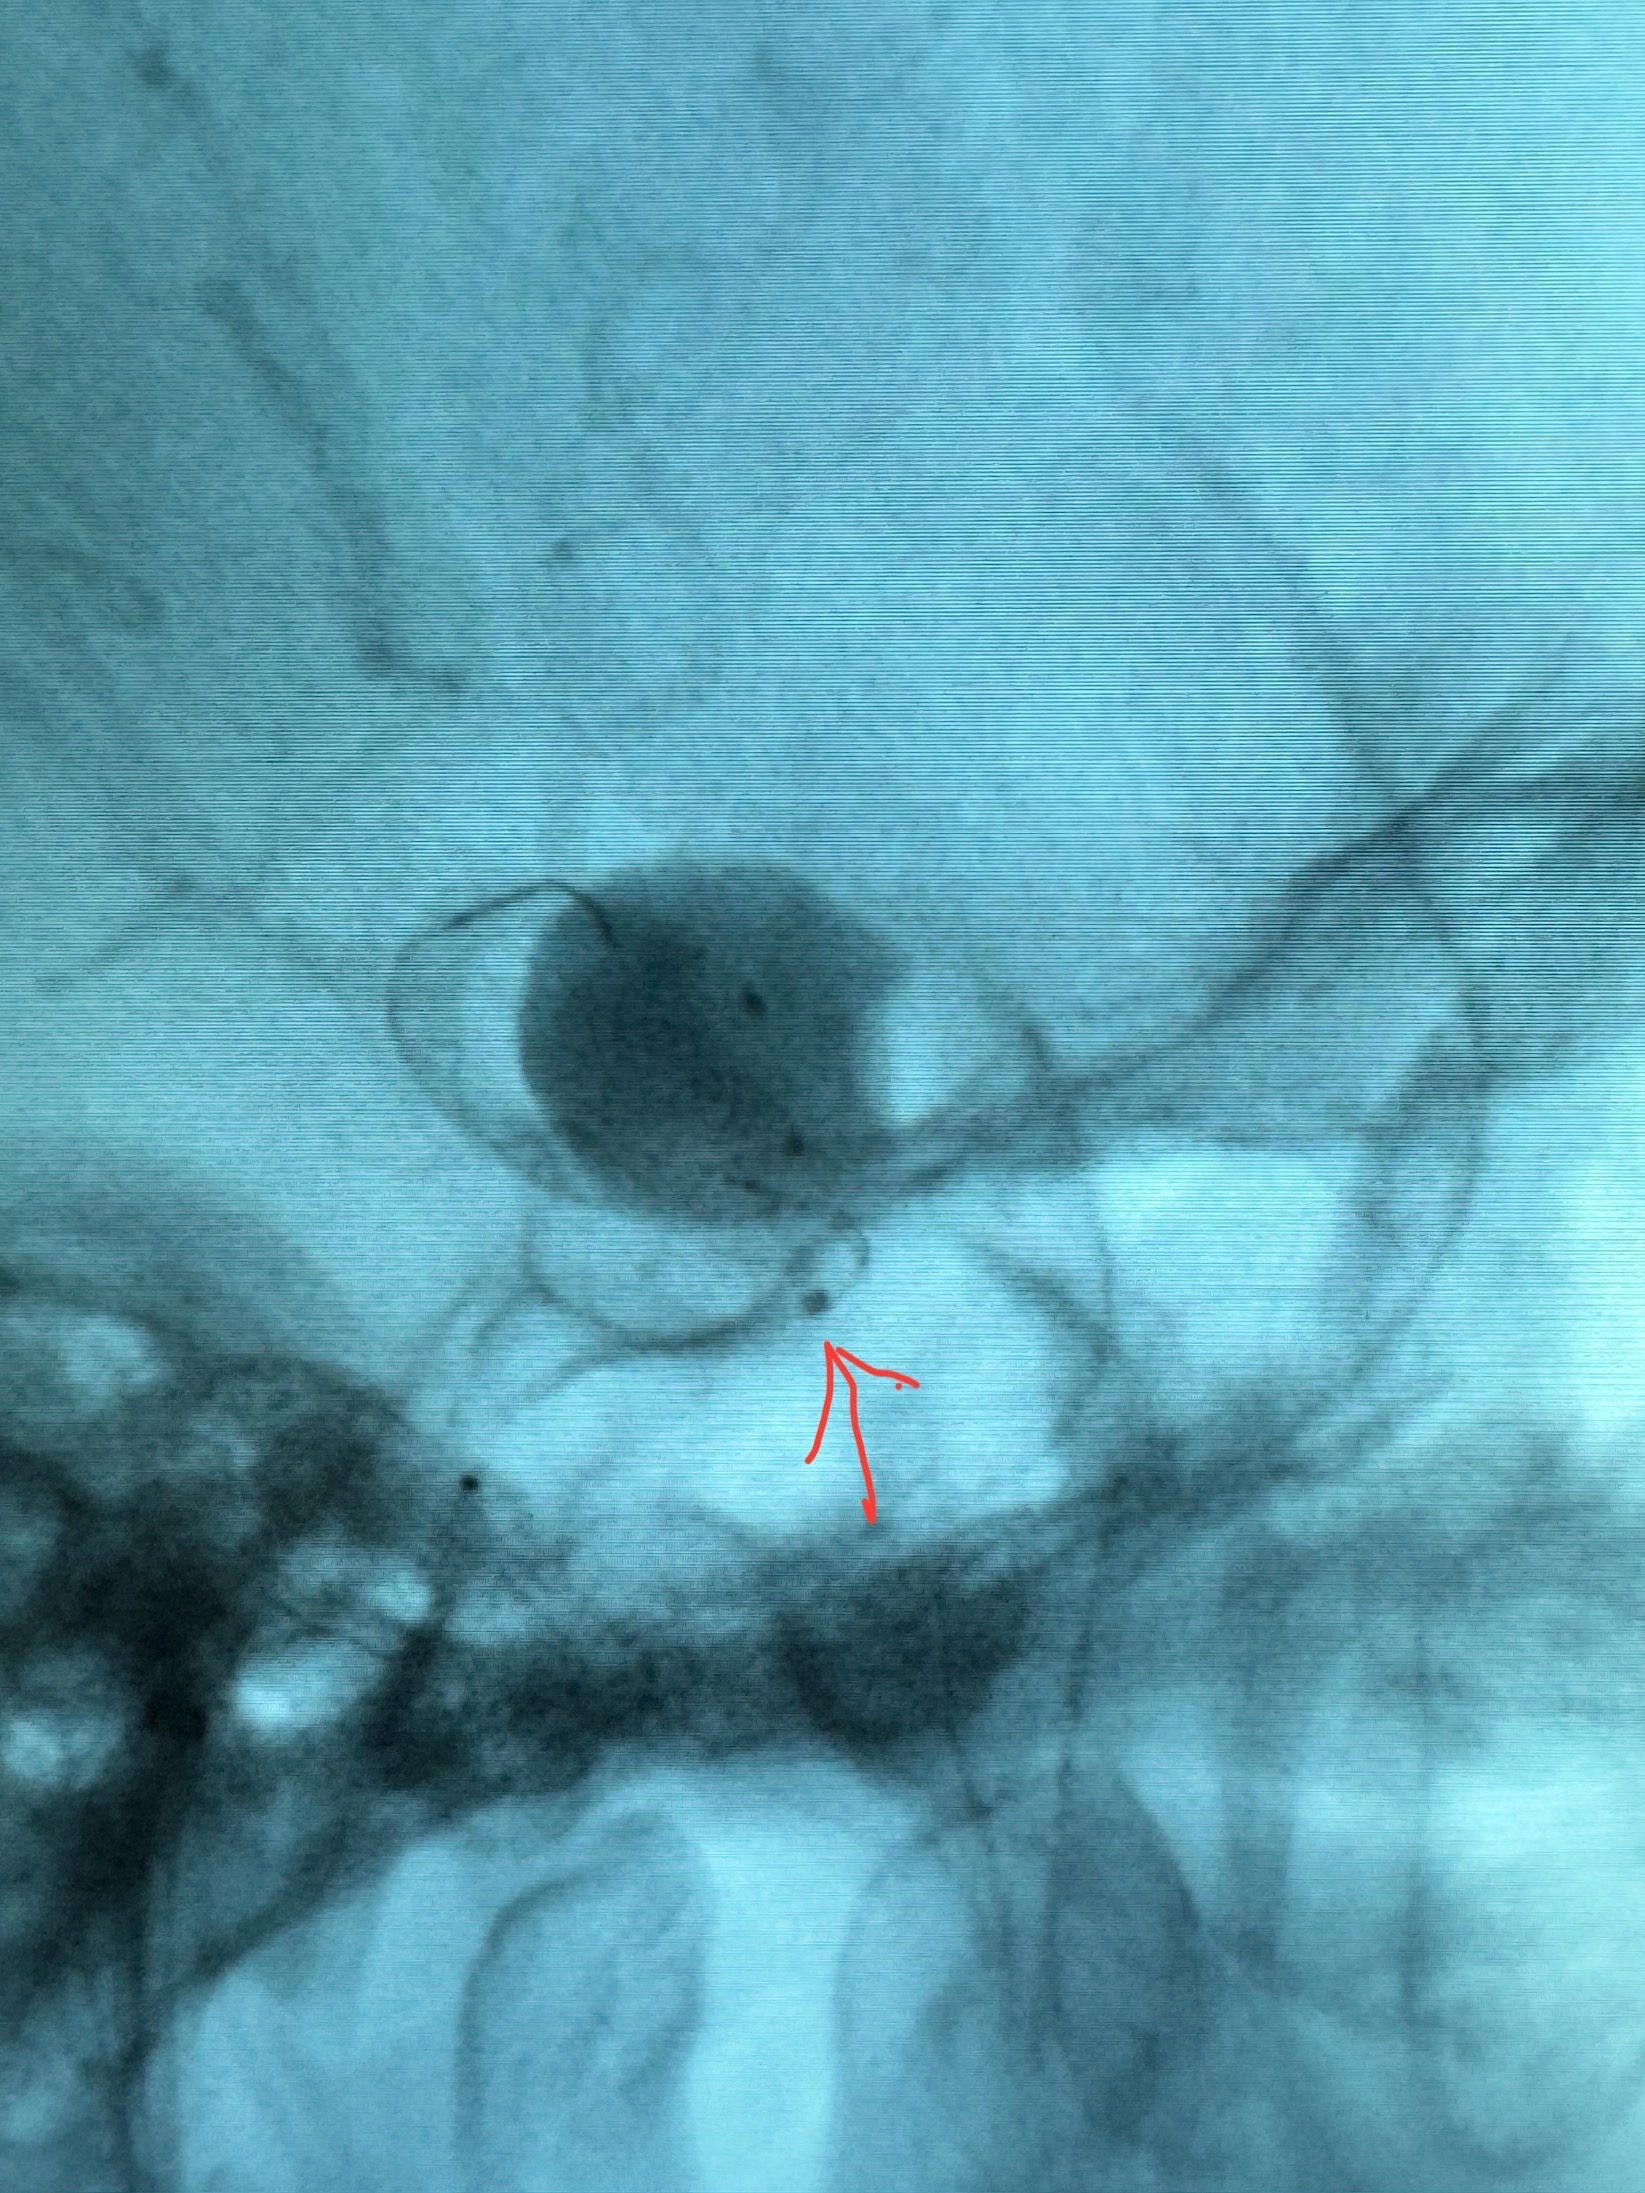

手推冒烟显示支架位置及展开情况,箭头为支架导管的位置

尝试回收支架失败,只能考虑释放支架了

逐帧图像展示歪着脖子释放支架,旁边吩咐助手手机摄影、拍照留像(透视机不能留影像)

看动脉瘤内造影剂滞留,未见明确射流,遂撤出预留的栓塞微导管,快速结束手术,经导引导管灌注替罗非班250ug。